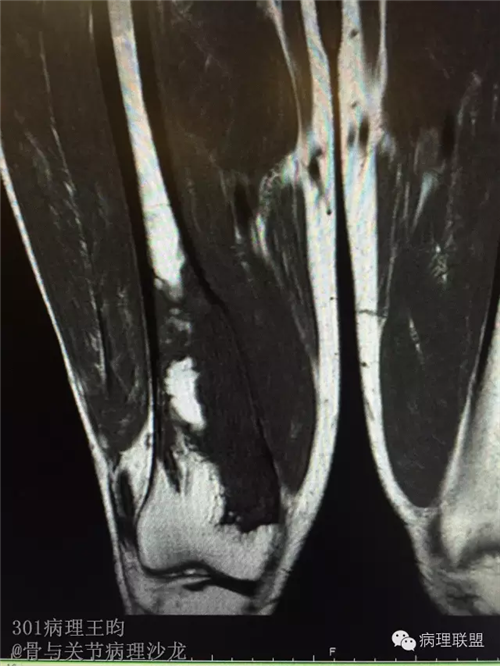

右股骨髓内高分化低级别骨肉瘤or骨纤维异常增殖症(Fibrous Dysplasia)?

男,36岁,活动后疼痛,发现右股骨远端肿瘤。